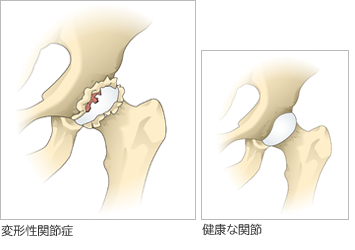

股関節の軟骨がすり減ることで痛みが生じる病気で圧倒的に女性に多いのが特徴です。骨の形の異常から二次的に発症するものが9割で、幼少期の股関節発育不全(臼蓋形成不全)のために骨盤側の受け皿の部分が浅いことが原因です。

〈正常な股関節〉

骨頭が球形で、関節に隙間がある

〈臼蓋形成不全〉

臼蓋の被りが浅い

〈変形性股関節症〉

関節の隙間が消失